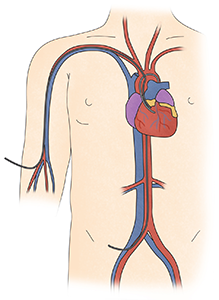

우심부전은 우심실 및 우심방의 압력 상승과 체순환계 울혈과 관련이 있습니다.

정상 우심실 기능은 전 부하, 후 부하, 우심실 수축력, 심실 상호 의존성 그리고 심장 리듬간의 상호 작용에 의해 결정됩니다. 우심부전은 우심실 후부하의 증가(폐색전, 저산소증, 대사성 산증) 혹은 우심실 수축력 저하(심근염, 우심 허혈), 전부하의 이상(삼첨판막 역류, 심낭 압전, 기계 호흡), 심실 상호 의존성 이상(삼첨판막 역류에 의한 용적 과부하) 등에 의해 발생합니다.